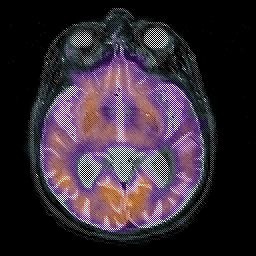

Alzheimer's disease, overlay -- Slice #22

[Home][Help][Clinical][Tour 1][Tour 2] Slice 22